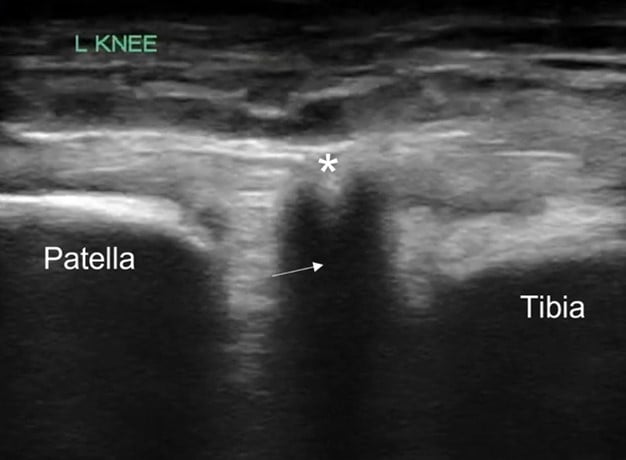

POCUS of the left knee was performed, which was concerning for a patellar tendon rupture and a joint effusion. (Figure 1 and Video 1) In addition, there was posterior acoustic shadowing obscuring part of the patellar tendon concerning for an avulsed bony fragment. (Figure 2) X-rays were performed, which confirmed the suspected diagnosis of a left tibial tubercle avulsion. (Figure 3) The patient was ultimately taken to the operating room for an Open Reduction and Internal Fixation (ORIF) by Orthopedic Surgery and discharged home the following day in a knee brace.

Figure 1. Ruptured patellar tendon (arrow) with joint effusion (*) seen in longitudinal view